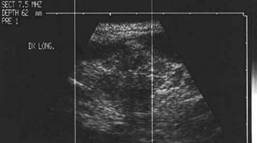

Tiroida normala

Ecostrutura omogena, normoecogena. Dimensiuni normale.

Se urmaresc rapoartele cu carotida, jugulara, muschii, traheea, esofagul.